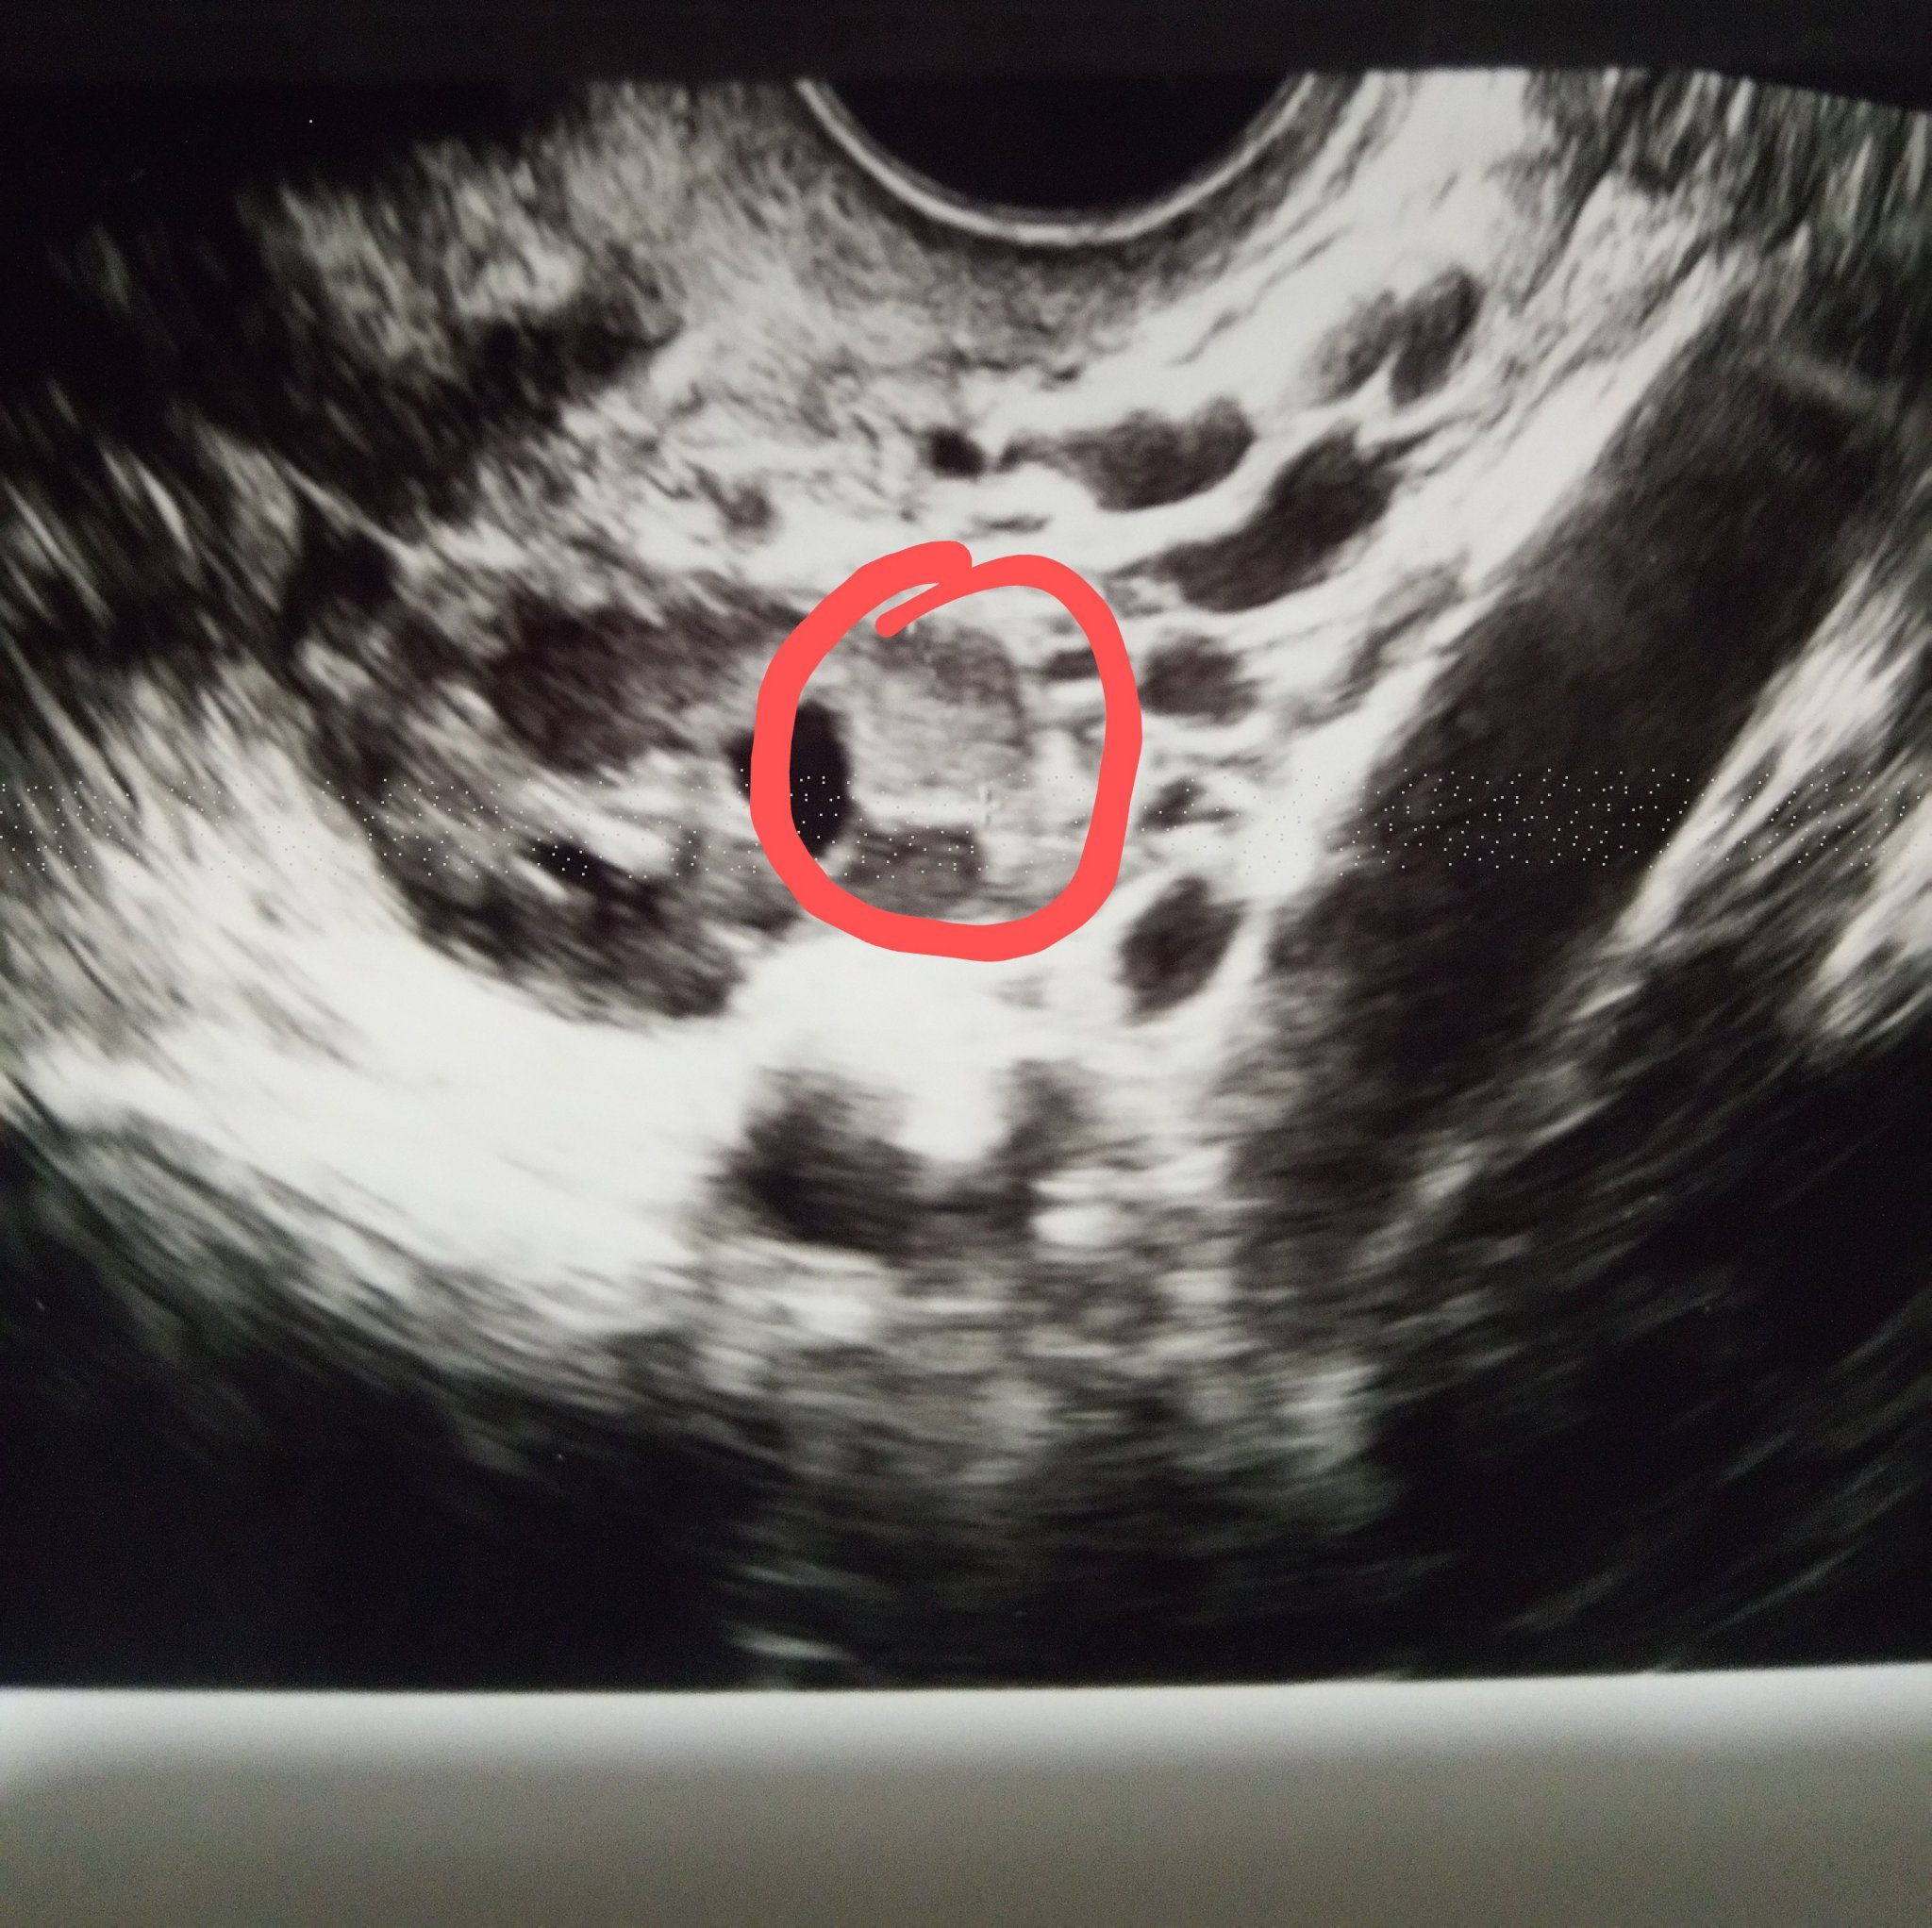

@Gabriela9 относно дали кистата е ендометриозна или не, по принцип и ти можеш да сравниш ако са ти дали снимка.

На мен първоначално обикновена АГ ми каза, че кистата е обикновена (фоликулярна) и така ми загуби 2,3 месеца. Чак след като не изчезна и си направих СА125 ми промени диагнозата. Аз вече се бях разлолебала в нейната преценка и един ден гледайки снимките търсех в нета да сравня с други кисти. Оказа се, че фоликулярните на ехограф са изцяло черни и хомогенни, ендометриозните са по-скоро сивкави (имат множество сиви малки точици). Можеш да потърсиш на английски endometrioma ultrasound (на images), както и за другите видове кисти, за да сравниш.

Да, ендометриозните са "уплътнени", тоест в средата имат сивкави петна, което означава, че са плътни, докато фоликулярните са изцяло кухи и стоят черни в средата. Но не само ендометриозните кисти са плътни, ами и хеморагиралото жълто тяло. Тоест, кистозно жълто тяло, което е пълно с кръв. Също и друг вид кисти, като дермоидни и тн са плътни. Реално, единствения начин да се разбере дали една киста е ендометриозна е с хистология, след оперативното и отстраняване. Повечето хирурзи са любопитни и при премахването я разрязват, при което изтича кафеникава "шоколадова" течност и разбират по това още преди хистологията. Но от патолог знам, че това е много грешно и компрометира хистологията и хирурзите, за да си задоволят собственото любопитство правят лоша услуга на пациентката. Но това е друга тема.

Ето я нагледно една от моите ендо кисти.Снимка от преди два месеца.Сивото е кистата,а черните петна са фоликулите.В момента съм с две,едната е сантиметър и половина,другата 0,94мм.Смятам,че на някой може да му е от полза да види точно как изглежда.